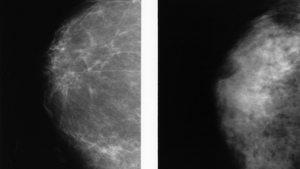

Two normal mammograms showing the difference between a dense breast (left) and a fatty breast (right). Photo credit: National Cancer Institute

Two normal mammograms showing the difference between a dense breast (left) and a fatty breast (right). Photo credit: National Cancer Institute